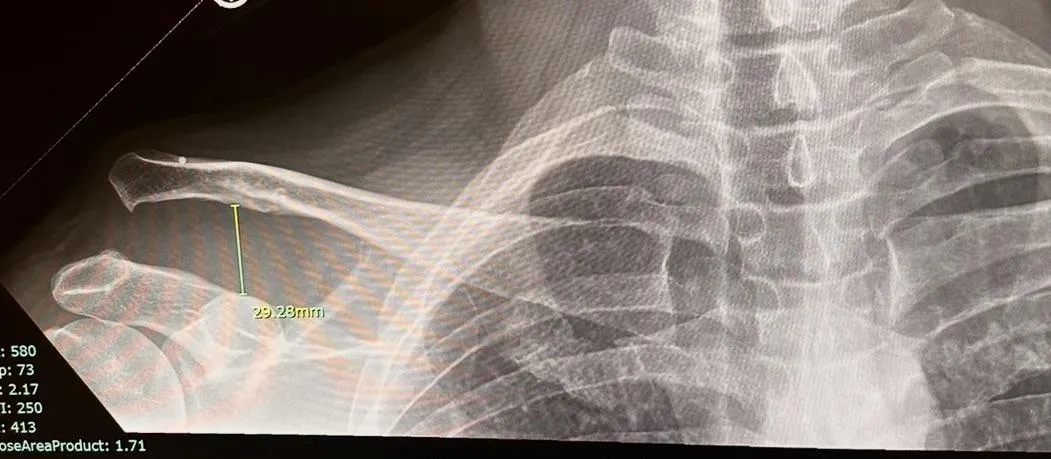

softball - Torn AC Joint, Torn Rotator Cuff, cracked scapula